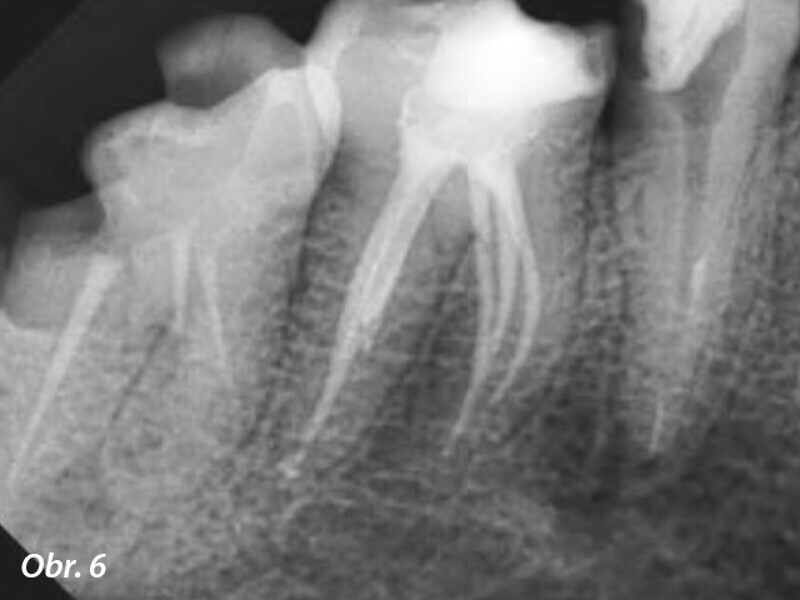

Endodontické ošetření s modulárním NiTi systémem